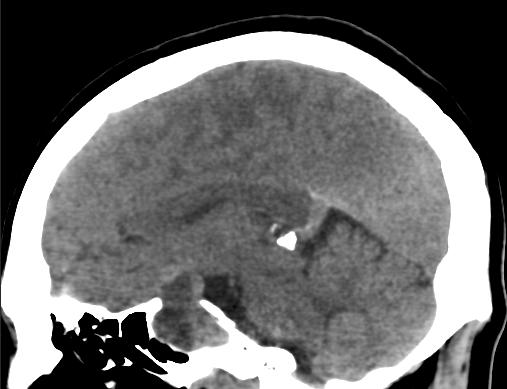

任何顱內(nèi)手術(shù)后在手術(shù)部位形成的血腫是較具損害性的并發(fā)癥,通常在24小時(shí)內(nèi)發(fā)展,如果不緊急處理,會(huì)導(dǎo)致嚴(yán)重的發(fā)病率甚至死亡。其主要原因是手術(shù)期間止血不足。據(jù)報(bào)道,開顱手術(shù)后其發(fā)生率為2.2%。在本研究中,有15名患者(10%)出現(xiàn)了這種并發(fā)癥。除泌乳素瘤組外,其他患者均無此并發(fā)癥,血腫形成幾乎均等分布。我們的觀察表明,這種并發(fā)癥與腫瘤的大小或手術(shù)時(shí)間無關(guān)。類似地,腫瘤的秘書或非秘書性質(zhì)與它的發(fā)生無關(guān)。我們無法找出催乳素瘤患者缺乏這種并發(fā)癥的原因。催乳素水平過高是否可以通過影響凝血系統(tǒng)為血腫形成提供某種保護(hù),或者僅說明這些患者可能是由經(jīng)驗(yàn)更豐富的神經(jīng)外科醫(yī)師進(jìn)行手術(shù)?這需要進(jìn)一步的探索。